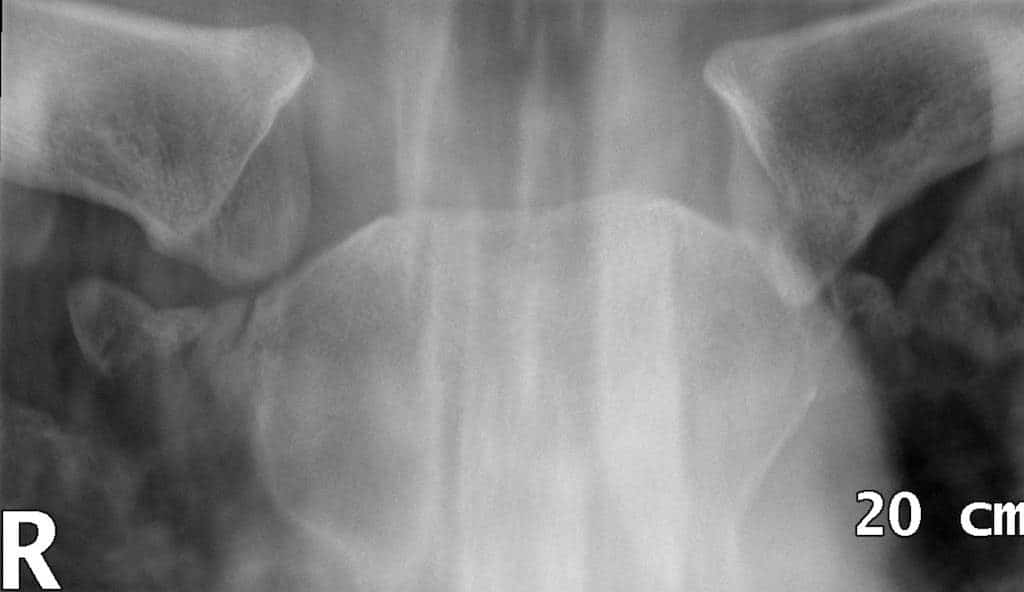

Dislocation of the Sternoclavicular Joint

Dislocation of the sternoclavicular joint is rare and requires significant force. The costoclavicular ligament and the articular disc are highly effective at absorbing and transmitting forces away from the joint into the sternum.

There are two major types of dislocation:

• Anterior dislocations (more common) – result from a blow to the anterior shoulder which rotates the shoulder backwards.

• Posterior dislocations (less common) – result from a force driving the shoulder forwards or from direct impact to the joint.

In adolescents, the epiphyseal growth plate of the sternal end of the clavicle has not fully closed. In this population, the dislocation is usually accompanied by a fracture through the plate.

Fig 1.2 - Radiograph of an sternoclavicular joint dislocation.

Radiograph of a right sternoclavicular joint dislocation.